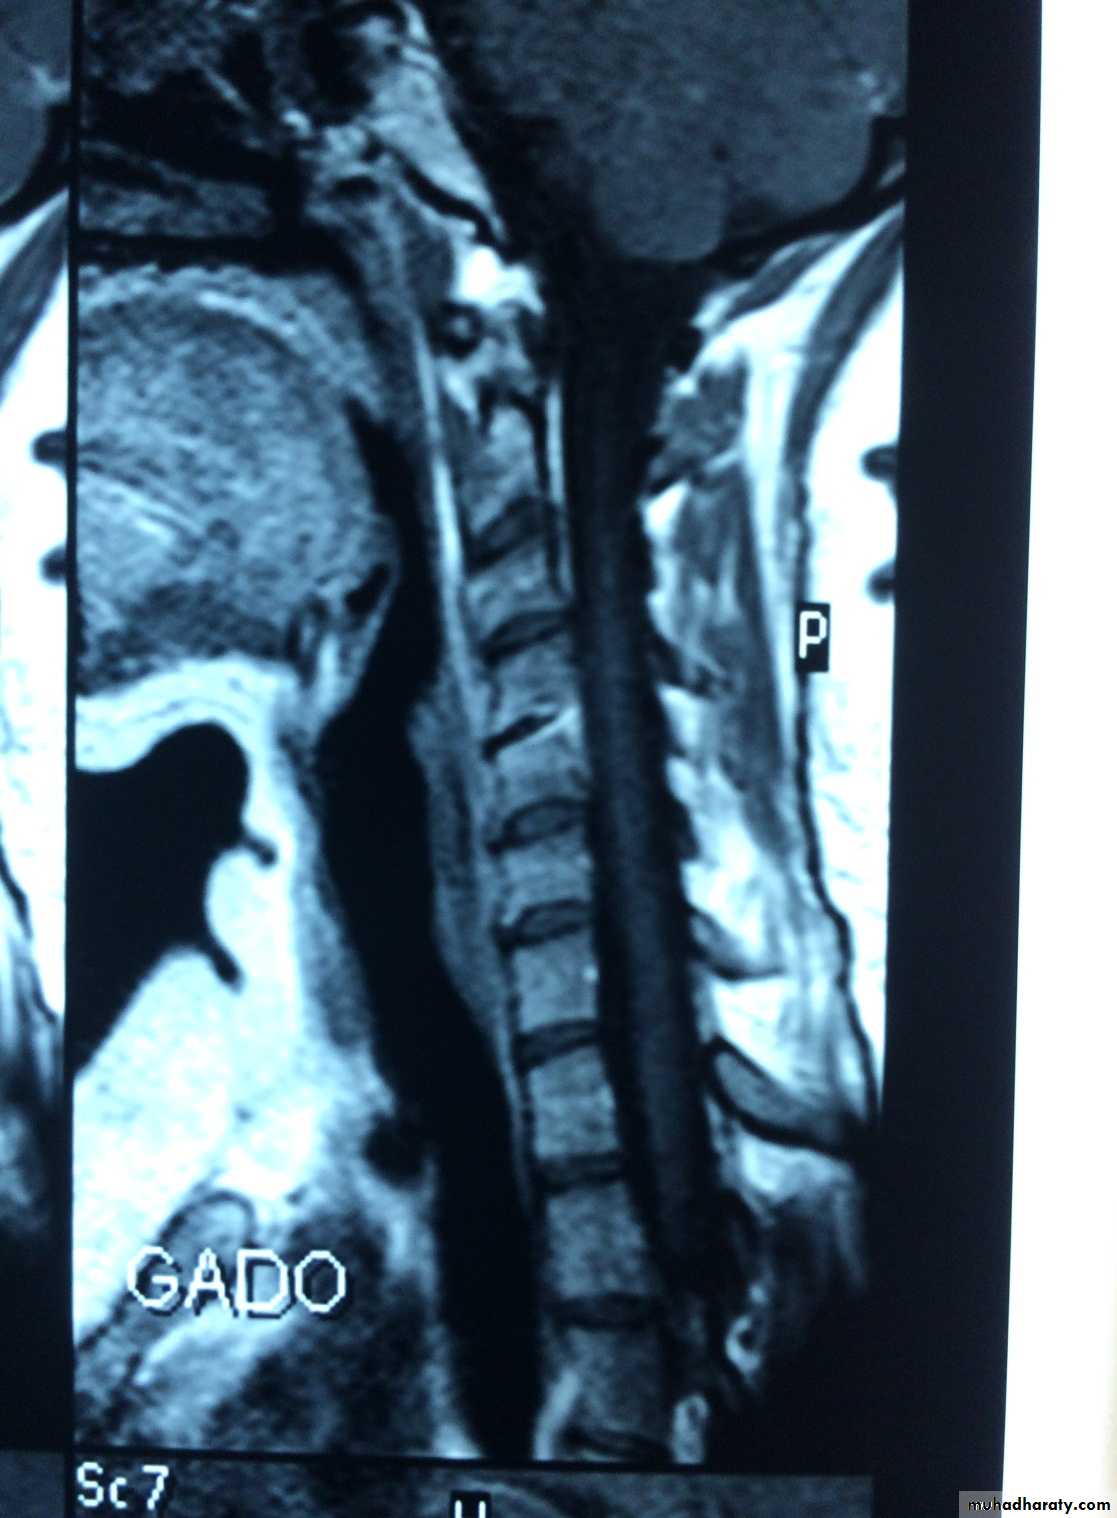

Discitis is an inflammation of the vertebral disc space often related to infection. Infection of the disc space must be considered with vertebral osteomyelitis, as these conditions are almost always present together and share much of the same pathophysiology, symptoms, and treatment. The lumbar region is most commonly affected, followed by the cervical spine and, lastly, the thoracic spineMRI with contrast before 1m.

MRI

INFECTIVE DISCITIS